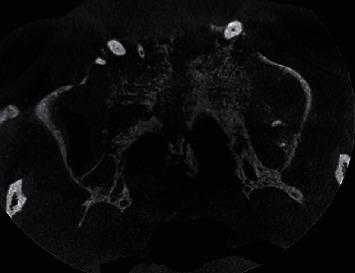

Polymorphous low-grade adenocarcinoma (PLGA) is a slow growing malignant tumor of minor salivary glands and is generally of indolent nature. However, according to the most recent WHO Classification of Salivary Gland Tumors (2017), the cancer is classified as Polymorphous AdenoCarcinoma (PAC). PAC presents as a less aggressive tumor, though it could on rare occasions demonstrate distant metastasis. . A 47-year-old man who was referred by a private practitioner for a CBCT scan in reference to a proliferative soft-tissue growth in the hard palate. The growth was mild and tender and there was Grade III mobility in relation to all the maxillary teeth. Panoramic radiograph taken previously had revealed evidence of alveolar bone loss in relation to the maxillary teeth and was inconclusive of any other findings. The CBCT scan revealed evidence of moth-eaten appearance of maxilla with destruction of medial and lateral walls and floor of maxillary sinus. There was also evidence of involvement of right eustachian tube, ethmoidal wall, and nasopalatine canal. An intraosseous malignancy of the palate was suspected, and a total maxillectomy was performed. The tissue sample was sent for histopathological assessment wherein changes diagnostic for polymorphous low-grade adenocarcinoma of the palate were observed.